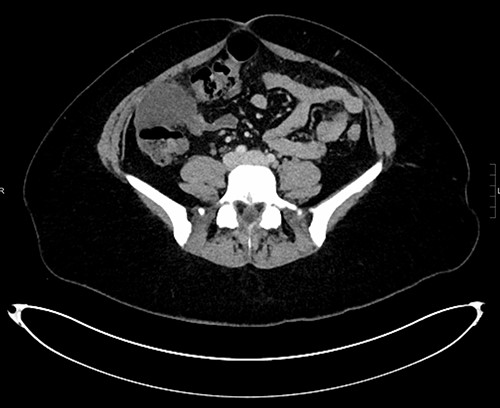

The patient’s symptoms improved, and she was discharged with outpatient follow-up. A subsequent CT abdomen 1 month later showed that the lesion remained unchanged. The patient then proceeded to diagnostic laparoscopy that revealed a multi-cystic structure overlying the distal ascending colon and hepatic flexure. The lesion was adherent to the epiploic appendages of the colon and in places was continuous with the omentum. The structure was dissected and removed whole (Fig. 4). Histology of the lesion demonstrated MCPM. The patient recovered from surgery well and will undergo a period of surveillance for return of her symptoms.